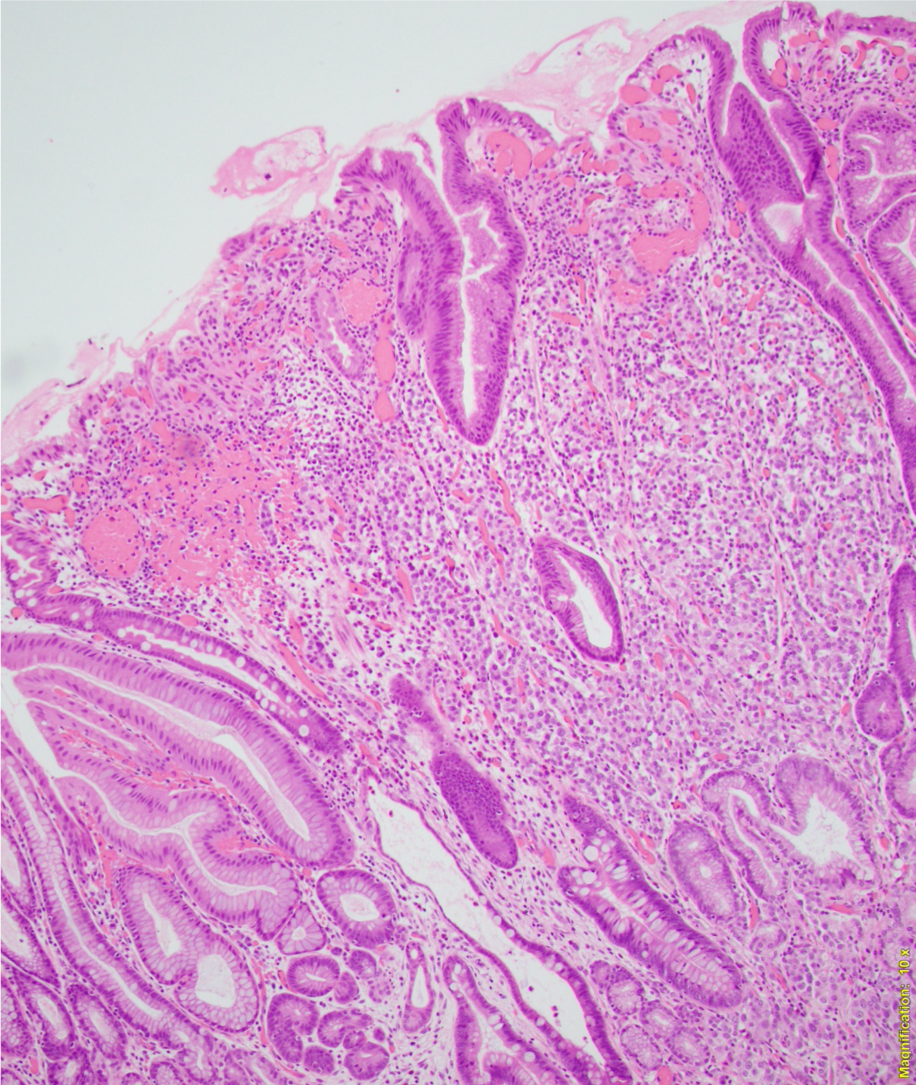

A 56-year-old female underwent upper endoscopy for dyspepsia. A 1 cm gastric nodule was found and biopsied. The histological findings are shown in Figure1 (low power) and Figure 2 (high power). Synaptophysin immunostaining of the tumor (Figure 3) and the background mucosa (Figure 4) are included.

This NET is occurring in a background of atrophic oxyntic mucosa, also known as autoimmune metaplastic atrophic gastritis ( AMAG), which typically shows nodular neuroendocrine cell hyperplasia (ECL) highlighted by synaptophysin stain ( Figure 4}. Intestinal metaplasia is also seen in Figure 1. Psedopyloric metaplasia (another characteristic) feature cannot be appreciated in the provided photographs. Even though Gastrin stain is not provided, the staining pattern of neuroendocrine cells is not that of G cells. Type 1 gastric NETs are typically small, multiple, low grade, associated with antibodies for intrinsic factor/ parietal cell, often have iron deficiency or B12 deficiency, and are managed by endoscopic surveillance. Type 3 NETs are sporadic, not associated with atrophic corpus gastritis. Type 2 are rare, can show ECL hyperplasia, but are associated with MEN1/gastrinoma and parietal cell hyperplasia.